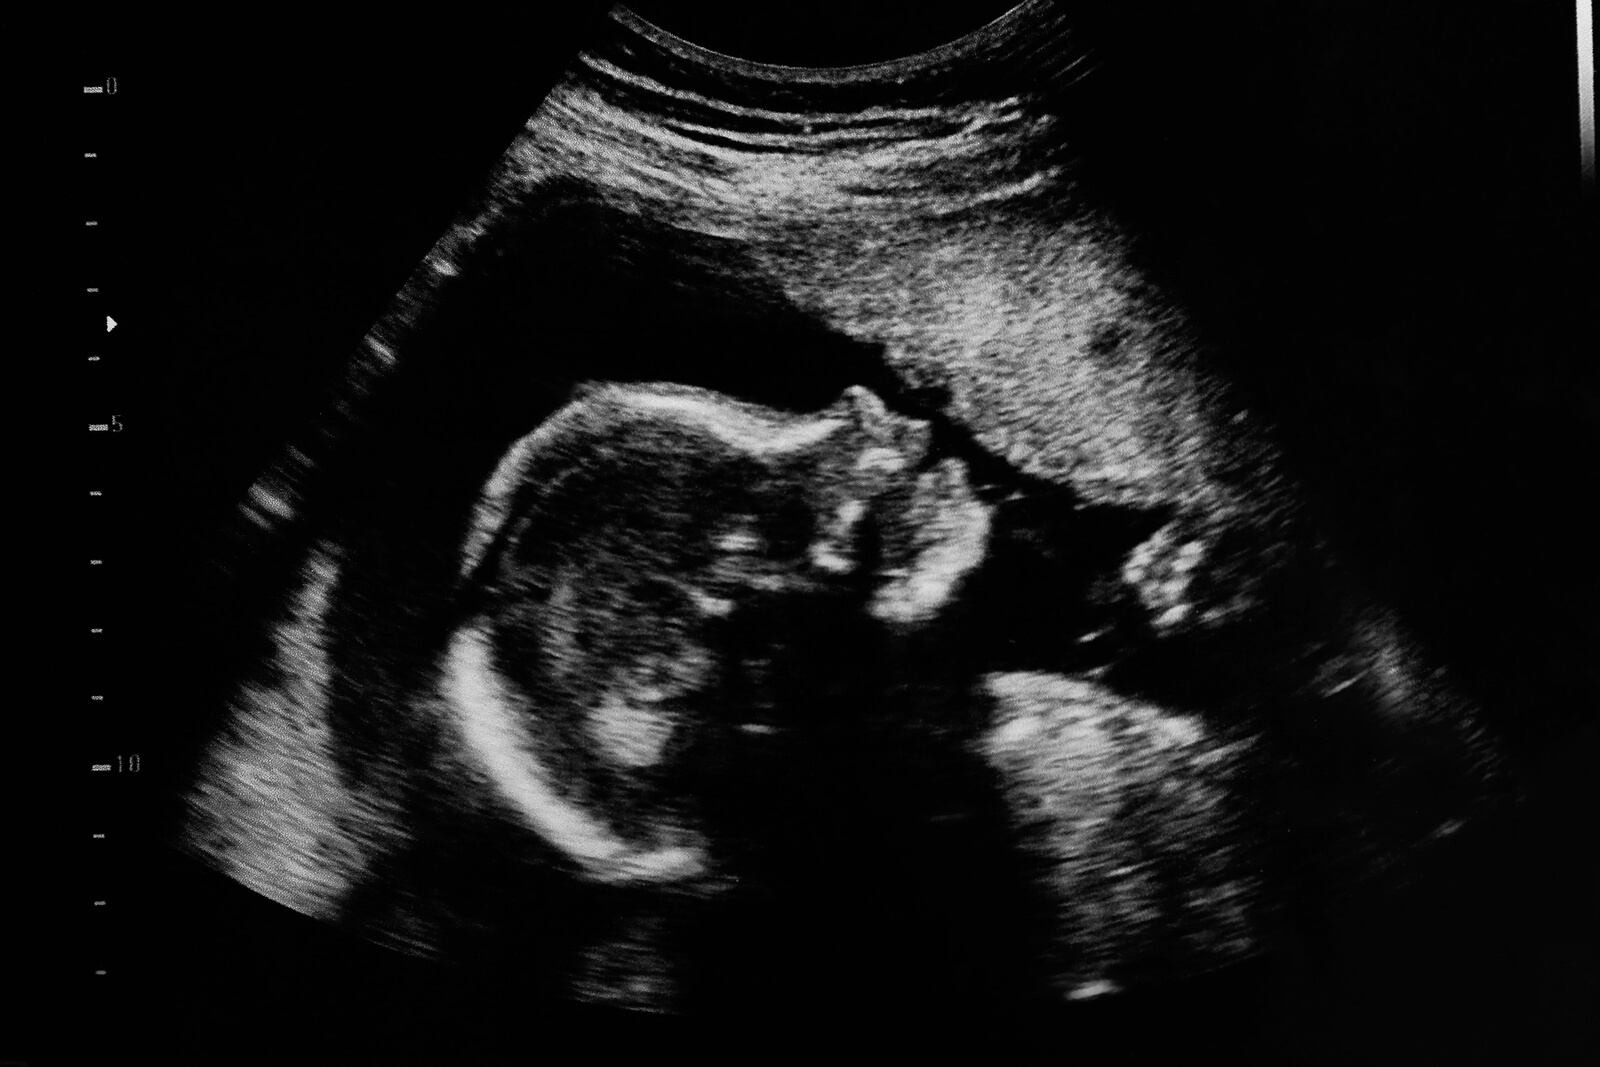

Si tratta di uno studio non invasivo che cerca di valutare come si sviluppa il corpo del bambino all’interno del grembo materno. Attraverso di essa è possibile rilevare tempestivamente alcune patologie fetali come le malformazioni congenite.

Questo studio viene effettuato tramite uno speciale dispositivo che emette onde sonore ad alta frequenza nell’addome della donna.

Il suono si disperde attraverso il liquido amniotico e “scontra” con le diverse strutture del bambino. Questo genera un segnale di risposta (eco), che viene catturato da un computer e visualizzato come un’immagine bidimensionale o tridimensionale del bambino.